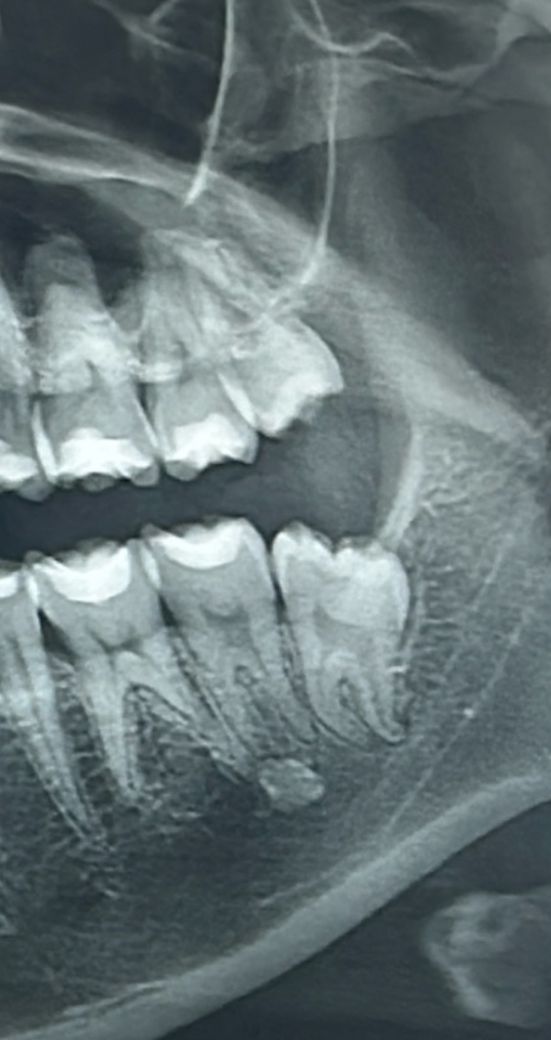

오늘 치과 방문해서 엑스레이 찍었는데 사진을 다시 보니 사랑니 앞 어금니 밑에 뭔가 보이네요… 치과에선 별말씀 없으셨는데 문제되는 건 아닌가요? 그리고 사랑니 발치 후 윗 부분 사랑니는 미발치 상태라 발치한 부분이 헐고 있는 게 느껴지는데 일반적인 경우인가요?

치조골 주변에는 특정 부위의 치조골이 밀도가 높은 경우가 있습니다. 그런 상황에서 저런 형태로 보이기 때문에 크게 문제가 되지는 않습니다.

사진에 보이는건 큰 문제가 잇는건 아니고 치아 밑 잇몸뼈가 다른사람보다 단단히 뭉쳐 잇는거라고 생각하시면됩니다.

1. 엑스레이 양상으로는 idopathic sclerosis로 치료가 필요하거나 하지 않습니다. 그냥 두시면 됩니다. 원인을 특정하기 어려운 치조골의 반응으로 생각하시면 됩니다.

2. 위 사랑니도 불편하다면 빼시면 될 것 같습니다. 보통 위, 아래 사랑니 같이 빼줍니다.